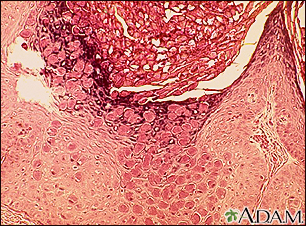

Molluscum - microscopic appearanceBackMolluscum - microscopic appearanceThis is how a molluscum lesion appears under microscopic examination. Molluscum are small, raised, pearly skin lesions caused by the molluscum virus, a member of the poxvirus family. E-mail FormEmail ResultsName:Email address:Recipients Name:Recipients address:Message: